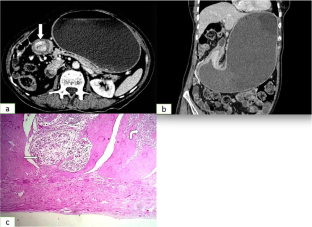

Fig. 3